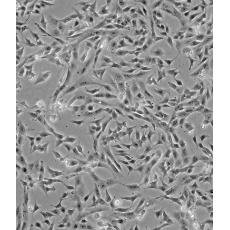

SK-N-SH [SKNSH]

中文名稱 人神經(jīng)母細(xì)胞瘤細(xì)胞

組織來源 神經(jīng)母細(xì)胞瘤;骨髓來源;女性

生長特性 adherent

形態(tài)特征 epithelial

細(xì)胞描述 SK-N-SH細(xì)胞系由J.L.Bieder建系,它與SK-N-MC所不同的是倍增時(shí)間較長且多巴胺-β-羥基酶水平較高。 SK-N-SH在細(xì)胞介導(dǎo)的細(xì)胞毒性試驗(yàn)中用作靶細(xì)胞系。